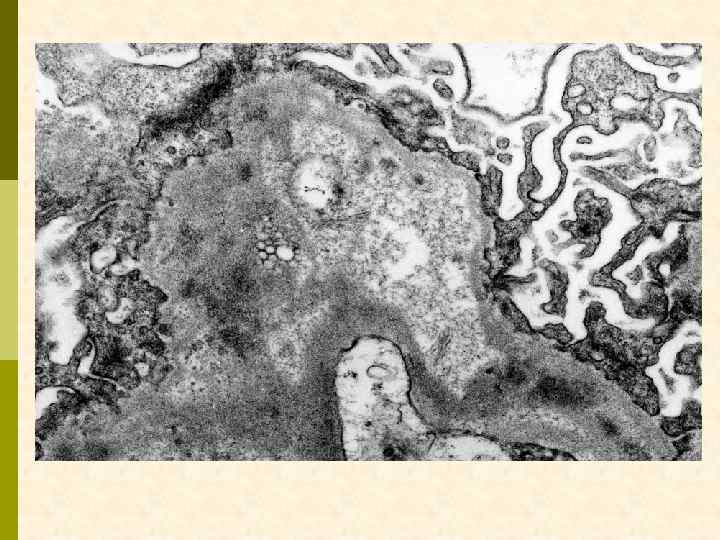

Характерные морфологические признаки ВИЧАН p почки больших размеров p тяжелое повреждение клубочков – коллаптоидный вариант ФСГС p расширение мезангия p гиперплазия и пролиферация подоцитов, аномалия висцерального и париетального эпителия клубочков – дедифференцирование ? ? ? p иммунные депозиты минимальны p атрофия канальцевого эпителия, кистозная дегенерация канальцев с заполнением их белковыми цилиндрами p нередкий тяжелый интерстициальный отек с моноцитарной (лимфоцитарной) инфильтрацией p нередко острый канальцевый некроз p ЭМ: тубуло-ретикулярные структуры в эндотелиоцитах клубочковых капилляров и других сосудов

ВИЧ-ассоциированная нефропатия. Тубулоретикулярные структуры в эндотелиоците.

депозиты в мезангии и в ГБМ, тубуло-ретикулярные структуры в эндотелиоците

тубуло-ретикулярные структуры в эндотелиоците